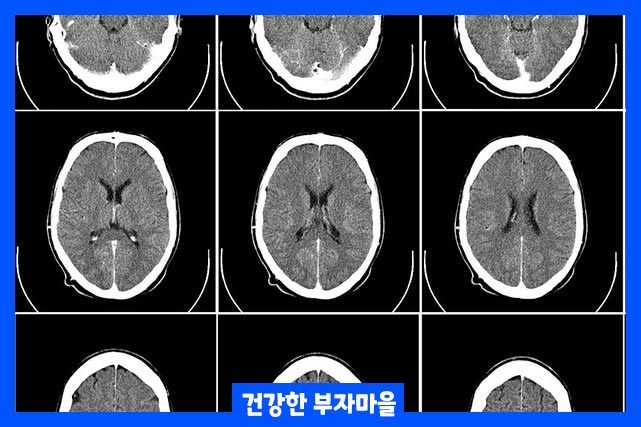

뇌졸중은 뇌로 가는 혈류가 차단되어 혈액이 공급되지 않을 때 발생합니다. 뇌는 혈액을 공급받지 못하면 필요한 산소와 영양분을 받지 못합니다. 그러면 뇌세포가 손상되거나 죽기 시작하는 증상을 말합니다.

뇌졸중에는 두 가지 주요 종류가 있습니다. 뇌로 가는 혈류가 차단되는 허혈성 뇌졸중, 머리의 충격 또는 질환으로 갑작스럽게 뇌에 출혈이 있는 출혈성 뇌졸중이 있습니다.

출혈성 뇌졸중은 머리에 충격을 받아 뇌혈관이 터지면서 출혈이 발생한 경우의 뇌내출혈이 발생하게 됩니다. 뇌내출혈이 발생하면 혈액이 뇌 조직으로 흘러들어 가면 뇌에 산소 공급을 원활하게 하지 못하거나 차단합니다.